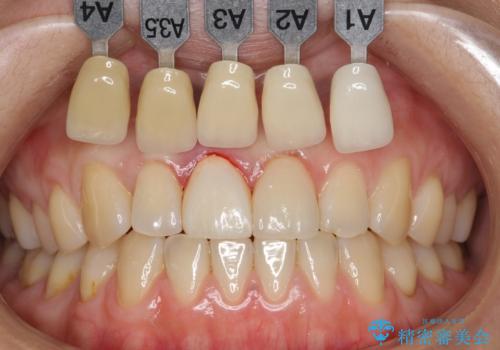

天然歯と見紛うほどの自然な仕上がりに大変喜んで頂けました。

隣在歯を模倣した表面性状・繊細なグラデーション・透明感による再現性の高いセラミッククラウンは、熟練した技工士さんの技術の賜物です。

ジルコニアクラウン エクセレント